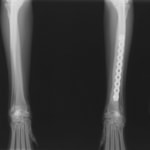

トイプードル 右遠位橈尺骨短斜骨折のALPSによる内固定

当院ではAdvanced Locking plate system(ALPS)と、Locking compression plate system(LCPS)という骨接合法で骨折症例の治療を行っています。

従来型のプレートのように広い面積で骨と接するプレートを用いて固定を行った場合、プレート下の骨はプレートとの接触面において血行が絶たれ壊死し、それがリモデリングされると骨密度が低下する。この骨密度の低下防ぐために、骨折部局所への血行を温存することの重要性が近年改めて認識されるようになってきている。Advaed Locking Plate System (ALPS)は従来型のプレートシステムの欠点を改良し、より使いやすく、より骨への血行を阻害しないようにというコンセプトで作られた。

- ロッキングスクリューと圧着型スクリュー(皮質骨スクリュー)の双方が使用できる